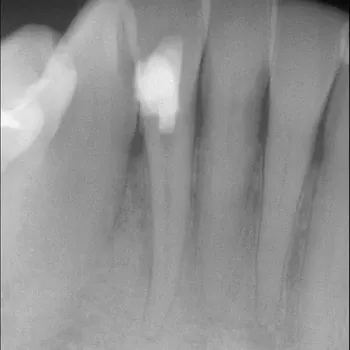

Fall 4: großer interradikulärer Entzündungsherd

Endodontie Fall 4: großer interradikulärer Entzündungsherd

Vor der Behandlung

Kontrolle nach Wurzelfüllung